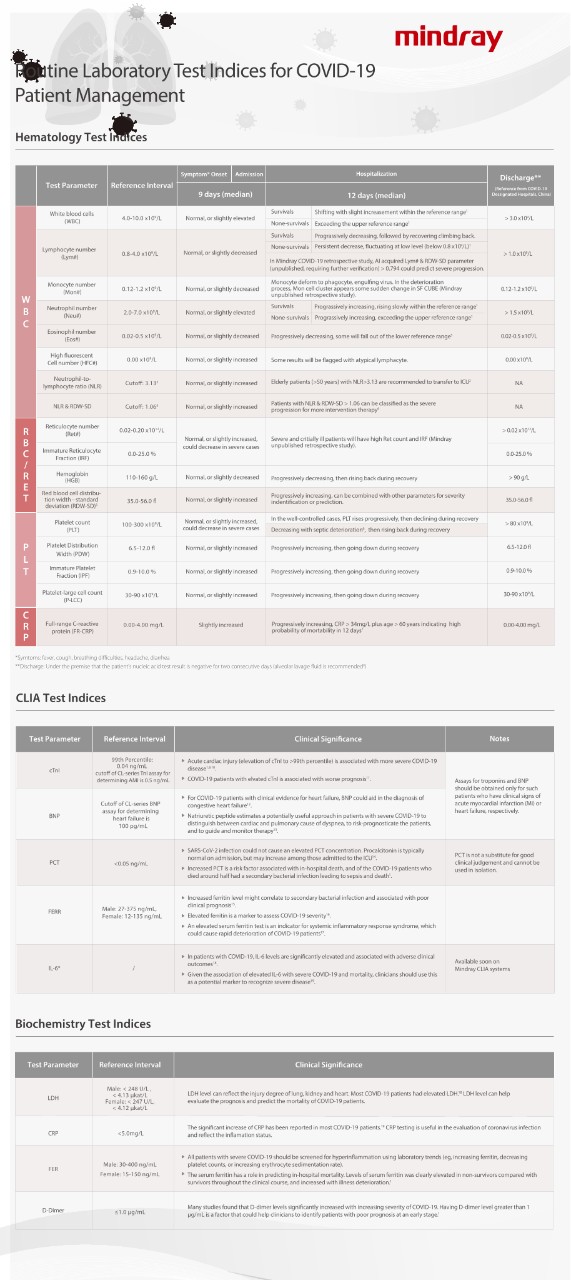

Hematology Test Indices

*Symtoms: fever, cough, breathing difficulties, headache, diarrhea

?

**Discharge: Under the premise that the patient's nucleic acid test result is negative for two consecutive days (alveolar lavage fluid is recommended8 )

?

?

CLIA Test Indices

Biochemistry Test Indices

References:

?

[1]. Fei Zhou, Ting Yu, et al. Clinical course and risk factors for mortality of adult inpatients with COVID-19, a retrospective cohort study. Lancet (2020). doi: 10.1016/S0140-6736(20)30566-3

[2]. Jingyuan Liu, Yao Liu, Pan Xiang, et al. Neutrophil-to-Lymphocyte Ratio Predicts Severe Illness Patients with 2019 Novel Coronavirus in the Early Stage. Medrxiv. doi: 10.1101/2020.02.10.20021584

[3]. Jin-jin Zhang, Xiang Dong, Yi-yuan Cao, et al. Clinical characteristics of 140 patients infected with SARSCoV-2, Allergy. 2020 Feb 19. doi: 10.1111/all.14238.

[4]. Wang CZ, NLR&RDW-SD: Indices for Identifying Severe COVID-19 Patients (to be published officially). /en/presscenter/NLR_RDW-SD__Indices_for_Identifying_Severe_COVID-19_Patients.html

[5]. Ephrem G., Red Blood Cell Distribution Width Should Indeed Be Assessed with Other Inflammatory Markers in Daily Clinical Practice. Cardiology. 2013;124(1):61. doi: 10.1159/000345925.

[6]. G. Lippi, M. Plebani, B. Michael Henry, Thrombocytopenia is associated with severe coronavirus disease 2019 (COVID-19) infections: A meta-analysis, Clinica Chimica Acta (2020). doi: 10.1016/j.cca.2020.03.022

[7]. Jiatao Lu, Shufang Hu, Rong Fan, et al. ACP risk grade: a simple mortality index for patients with confirmed or suspected severe acute respiratory syndrome coronavirus 2 disease (COVID-19) during the early stage of outbreak, medRxiv. doi: 10.1101/2020.02.20.20025510

[8]. Xiao-Hong Yao, Zhi-Cheng He, Ting-Yuan Li, Hua-Rong Zhang, et al. Pathological evidence for residual SARS-CoV-2 in pulmonary tissues of a ready-for-discharge patient. Cell Research (2020) 0:1ŌĆō3. doi: 10.1038/s41422-020-0318-5

[9]. Wang D., Hu B., Hu C., et al. Clinical characteristics of 138 hospitalized patients with 2019 novel coronavirus-infected pneumonia, JAMA, 2020.

[10]. Lippi G., Lavie C.J., Sanchis-Gomar F. Cardiac troponin I in patients with coronavirus disease 2019 (COVID-19): Evidence from a meta-analysis. Prog Cardiovasc Dis, 2020.

[11]. Ruan Q., Yang K., Wang W., Jiang L., Song J. Clinical predictors of mortality due to COVID-19 based on an analysis of data of 150 patients, Intensive Care Med, 2020.

[12]. James L. Januzzi Jr. American College of Cardiology: Troponin and BNP use in COVID-19.

[13]. Kunal Mahajan, Prakash Chand Negi. The role of natriuretic peptide estimation in severe COVID-19.Monaldi Archives for Chest Disease, 2020.

[14]. Interim Clinical Guidance for Management of Patients with Confirmed Coronavirus Disease (COVID-19). US CDC.

[15]. Bo Zhou, et al. Utility of Ferritin, Procalcitonin, and C-reactive Protein in Severe Patients with 2019 Novel Coronavirus Disease.

[16]. Clinical guide for the management of critical care for adults with COVID-19 during the coronavirus pandemic. UK NHS.

[17]. Colafrancesco S, et al. COVID-19 gone bad: A new character in the spectrum of the hyperferritinemic syndrome?. Autoimmun Rev. 2020.

[18]. Coomes E, et al. Interleukin-6 in COVID-19: A Systematic Review and Meta-Analysis. doi: https://doi.org/10.1101/2020.03.30.20048058

[19]. Aziz M, Fatima R, Assaly R. Elevated Interleukin-6 and Severe COVID-19: A Meta-Analysis. J Med Virol. 2020.?